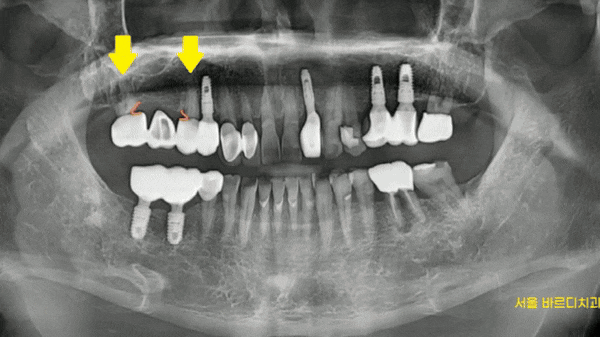

x-ray 를 우선 찍어보니

충치가 먹은게 보였습니다.

230313